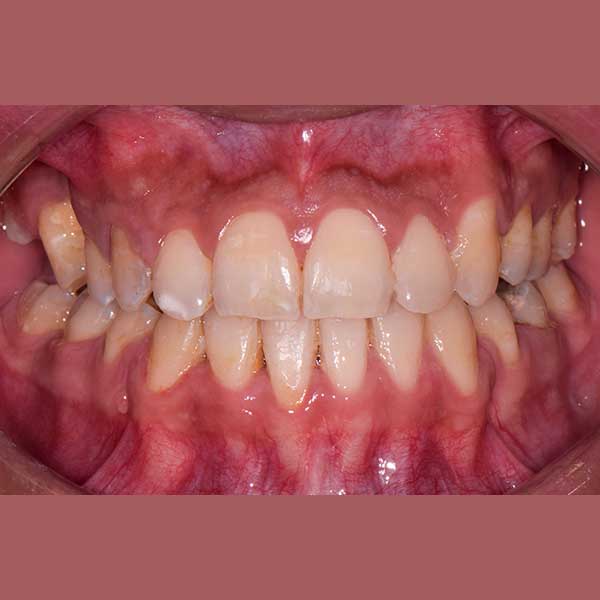

BEFORE

“راجعتني هذه الشابة قبل عدة سنوات وهي تعاني من ازدحام شديد في أسنانها، لدرجة أن أحد أنيابها قد بزغ بشكل مرتفع وبعيد عن مكانه الطبيعي. طلبت مني صديقتنا مساعدتها وترتيب أسنانها ولكن من دون قلع أسنان.

ولحسن الحظ في حالتها كان بالإمكان اجراء المعالجة من دون قلع أسنان، وقد اخترت استخدام التقويم ذاتي الربط (تقويم الدايمون) لأنه يساعد في تحريك الأسنان وتوسيع الفكين. وبالفعل، في نهاية العلاج نجحنا في رصف الأسنان بشكل ممتاز، وبات بإمكان مراجعتنا الابتسام بثقة وسعادة مجدداً.